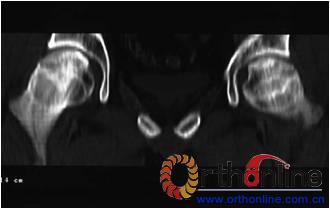

病灶修复情况比较,加用BMP2组病灶修复的完全性及硬化骨数量普遍优于未加BMP2组。(图3)

图3-2 女,30岁,SARS患者骨坏死,(1)术前MRI示双侧骨坏死;右Ⅱc期C3型,左Ⅱb期B型,打压植骨术(加BMP2),(2)5年后CT显示病灶修复好,关节功能优